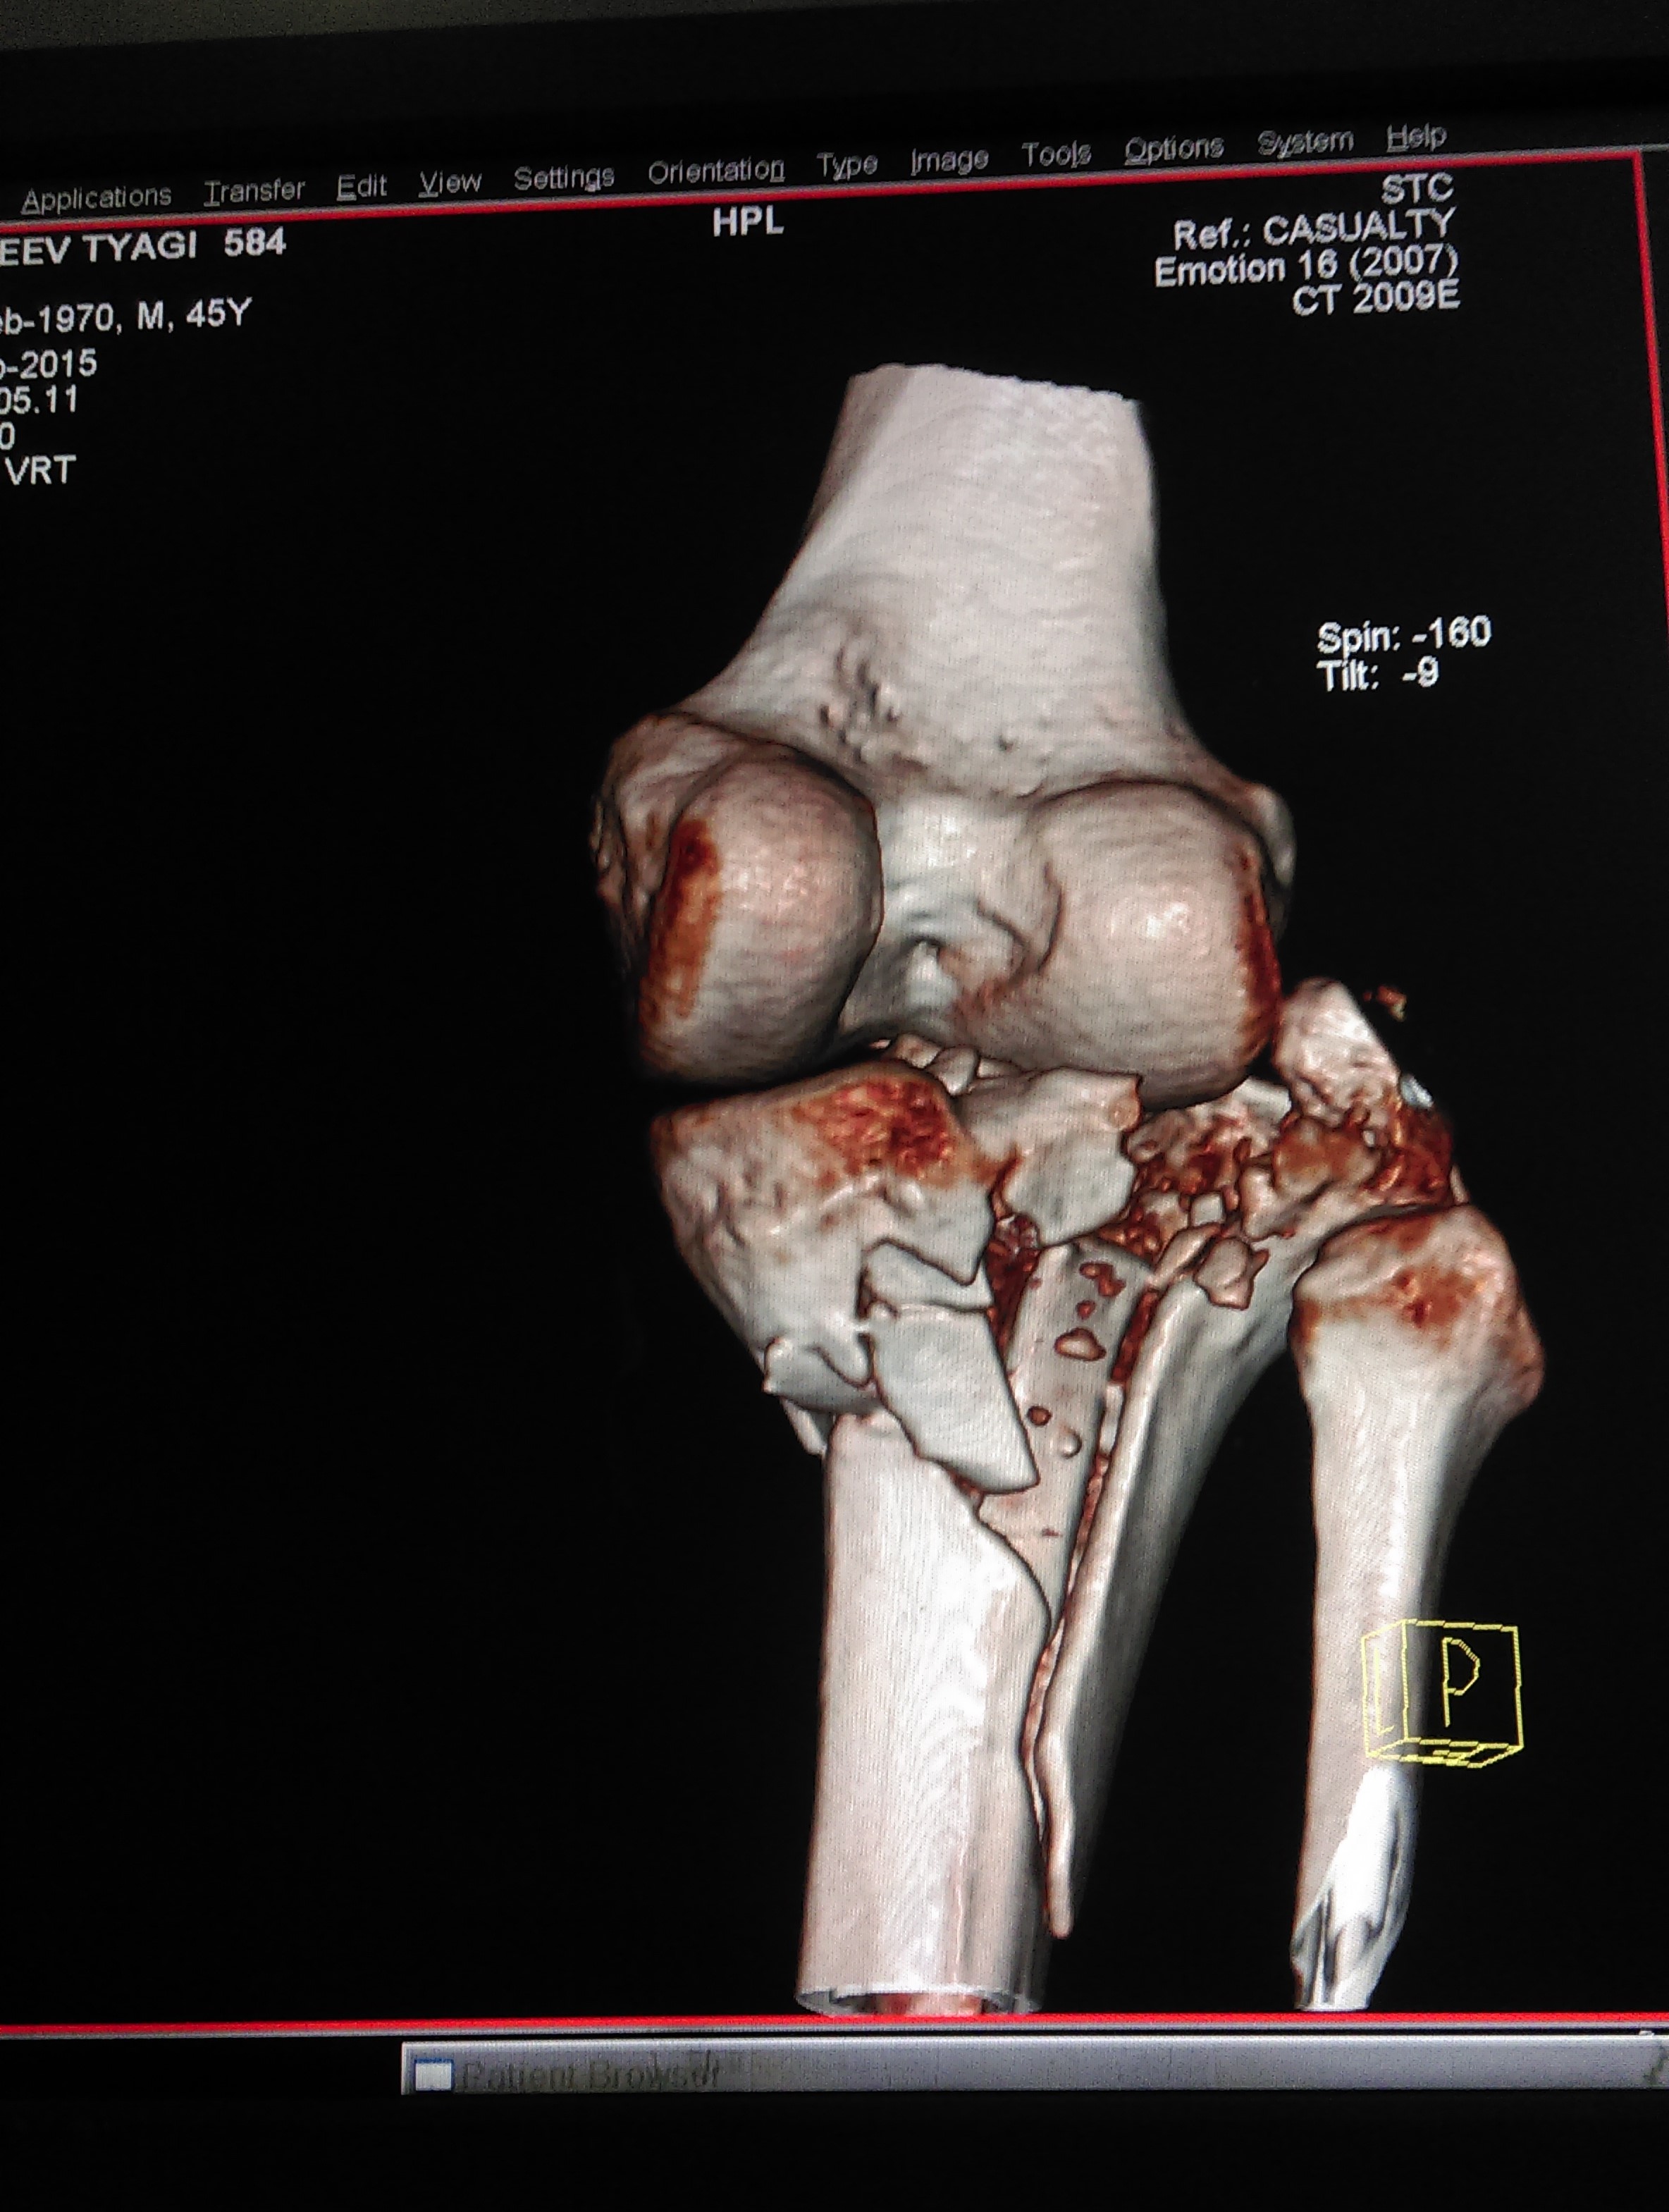

What is multi-ligament knee Injury?

Multiple ligament knee injuries happen when more than one of the knee’s ligaments is torn. They are less common than single ligament injuries.

What causes Multi-Ligament Knee Injury?

Multiple ligament knee injuries can occur during sports activities or through high-energy trauma, such as a fall from height or a car accident.

How Multi-ligament knee Injury diagnosed?

The most important way to initially diagnose these injuries is to review a thorough history with the patient to recall that their knee felt that it dislocated and slipped back in. It’s important to determine if this was solely their kneecap joint where there was a patellar (kneecap) dislocation or if it was the complete knee joint itself slipping out of place.

These injuries are very severe and potentially limb and life threatening. Thus, assessing for this and insuring that the patient’s knee function is intact, including both the status of the pulses to ensure that the artery is not injured as well as their sensation to ensure that there are no nerve injuries present is important.